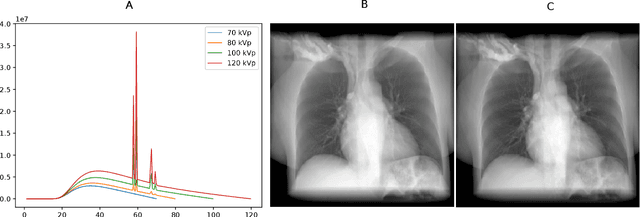

Estimating the lung depth on x-ray images could provide both an accurate opportunistic lung volume estimation during clinical routine and improve image contrast in modern structural chest imaging techniques like x-ray dark-field imaging. We present a method based on a convolutional neural network that allows a per-pixel lung thickness estimation and subsequent total lung capacity estimation. The network was trained and validated using 5250 simulated radiographs generated from 525 real CT scans. Furthermore, we are able to infer the model trained with simulation data on real radiographs. For 35 patients, quantitative and qualitative evaluation was performed on standard clinical radiographs. The ground-truth for each patient's total lung volume was defined based on the patients' corresponding CT scan. The mean-absolute error between the estimated lung volume on the 35 real radiographs and groundtruth volume was 0.73 liter. Additionally, we predicted the lung thicknesses on a synthetic dataset of 131 radiographs, where the mean-absolute error was 0.27 liter. The results show, that it is possible to transfer the knowledge obtained in a simulation model to real x-ray images.